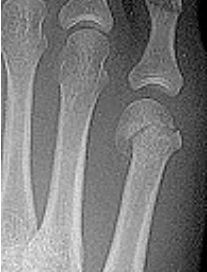

| What disease is this? What is shown by A, B and C? | Psoriatic arthritis. A = destructive changes B = Pencil in cup deformity C = IPJ fusion |

| What disease is this? | Psoriatic arthritis |